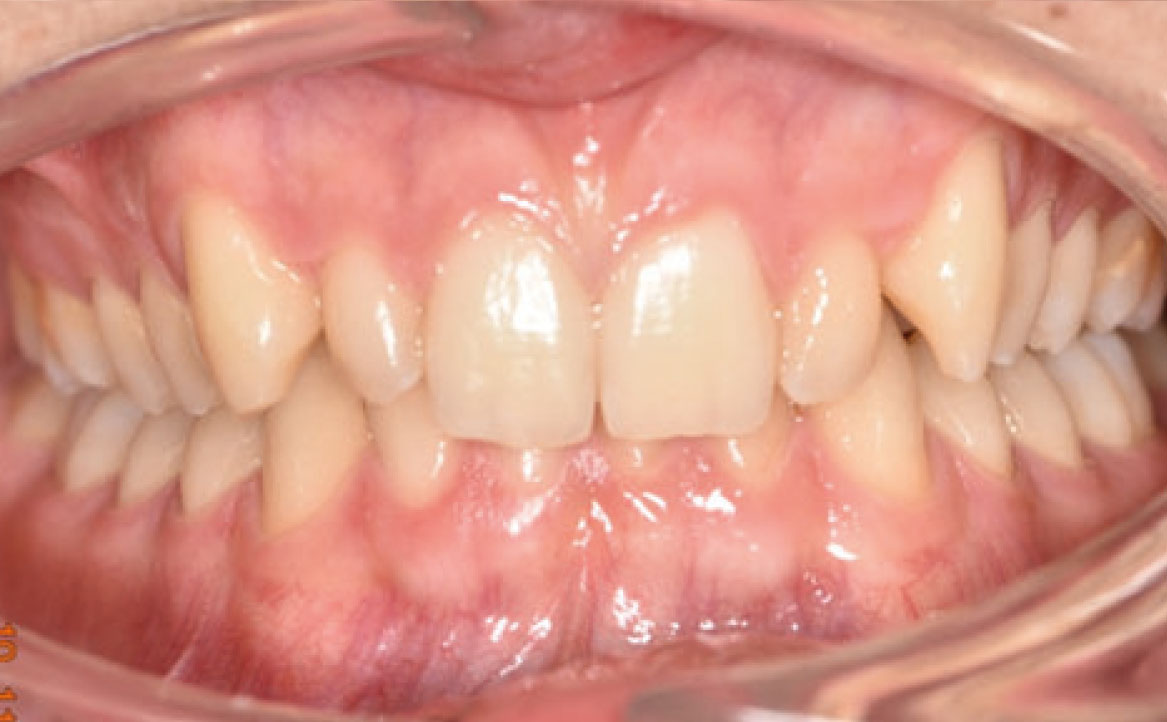

Il paziente si è presentato per la sua prima visita presso il reparto di Odontoiatria e Protesi Dentaria dell’Ospedale Vita-Salute San Raffaele diretto dal prof. E. F. Gherlone. All’esame obiettivo era evidente una malocclusione scheletrica e dentale di classe II associata a morso profondo e lieve affollamento anteriore superiore. In particolare, sono stati segnalati: rapporti occlusali di classe II, morso profondo, perdita di overjet, contrazione dell’arcata superiore e inferiore con leggero affollamento (fig. 1a-f). La richiesta del paziente era quella di migliorare l’estetica dei denti anteriori con allineatori invisibili di tipo Invisalign. Tuttavia, sia il paziente che il genitore sono stati informati che, per ragioni di efficacia e risoluzione del problema, era necessario agire anche a livello di funzionalità e risoluzione della malocclusione.

In primo luogo, sono stati prescritti entrambi gli esami radiografici ortodontici: OPT e teleradiografia latero-laterale del cranio (fig. 2a-b). Successivamente, in accordo con il genitore, è stata concordata una terapia ortodontica in due tempi. L’inizio della terapia è stato effettuato con Carriere Motion ed elastici di classe II, con l’obiettivo di migliorare la classe molare (fig. 2c-e).

Infatti, durante il primo controllo due mesi dopo, è stato osservato un miglioramento della classe molare (fig. 3a-c).